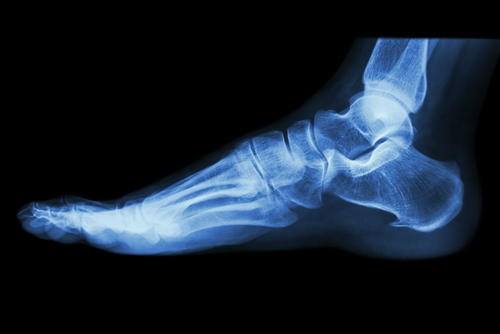

Nous avons la chance de le posséder la radiographie numérique à la Clinique Podiatrique St-Nicolas afin d'être plus précis dans nos diagnostics. N'hésitez pas à consulter notre podiatre pour toutes les douleurs des pieds et des chevilles.